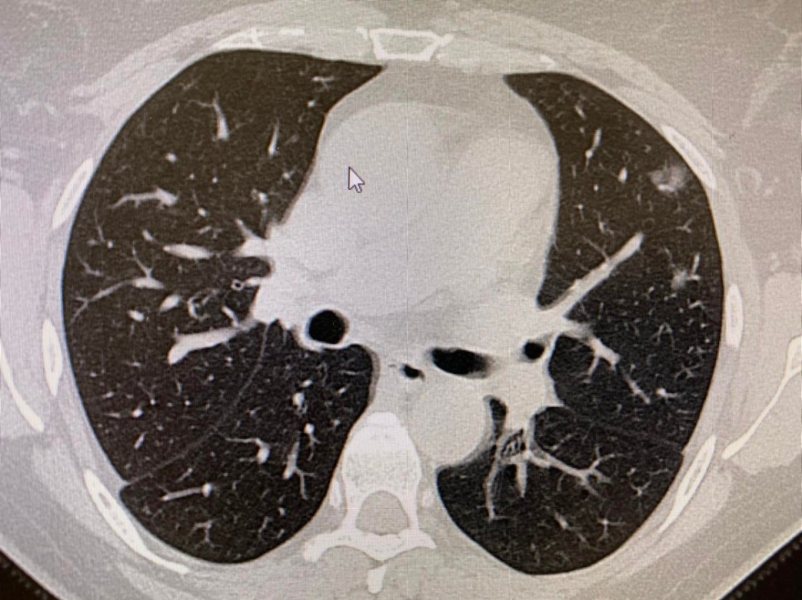

Dziewięciu było zaszczepionych. Na moją szczególną uwagę zwróciło jedno podwójne przyjęcie. 50 letni ojciec z 30 letnim synem mieszkający w jednym gospodarstwie domowym. Ojciec zaszczepiony dwiema dawkami szczepionki, syn nie został zaszczepiony. W TK klatki piersiowej. 50-letni Pacjent po szczepieniu - zmiany w płucach 1%, 30-letni syn bez szczepienia - zmiany w płucach 50%. Jest to jeden z wielu przykładów pokazujący, że szczepienia są ważne i należy się szczepić.

1 zdjęcie: 1% zajętych płuc.